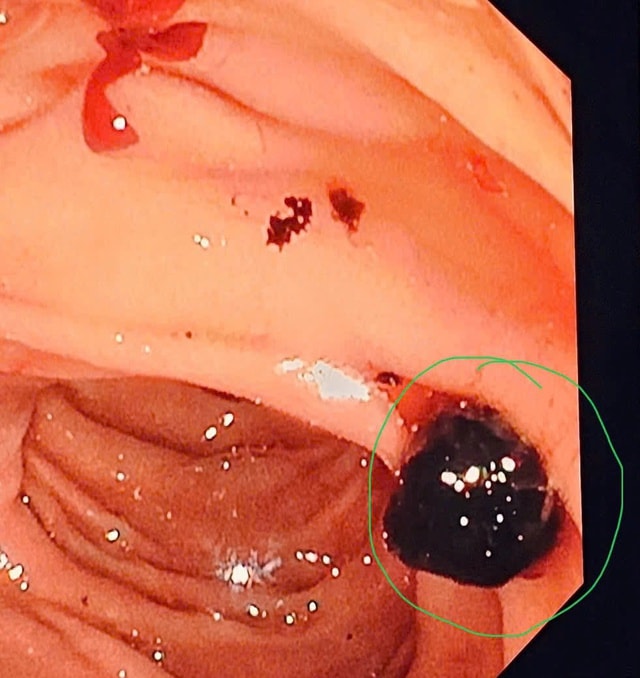

Mới đây, Bệnh viện Đa khoa tỉnh Thanh Hóa tiếp nhận người đàn ông 72 tuổi, trong tình trạng đau bụng vùng thượng vị và hạ sườn phải, đau âm ỉ liên tục tăng dần, ăn uống khó tiêu, mệt mỏi. Qua thăm khám và làm các xét nghiệm cận lâm sàng, bệnh nhân được chẩn đoán tắc ống mật do sỏi mật. Hình ảnh nội soi cho thấy có hai viên sỏi đường mật với kích thước lần lượt khoảng 6mm và 7mm. Bệnh nhân được tiến hành nội soi mật tụy ngược dòng can thiệp (ERCP) để lấy sỏi, giải phóng tắc nghẽn đường mật. Sau can thiệp, sỏi được lấy ra thành công, đường mật lưu thông tốt, bệnh nhân hết đau, ăn uống trở lại bình thường và được ra viện trong tình trạng ổn định.